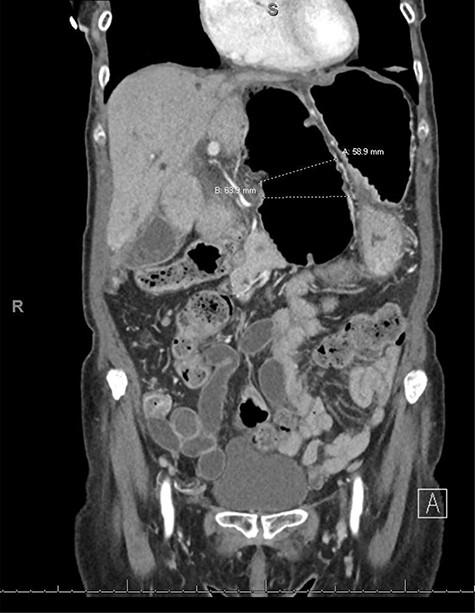

An 80-year-old female with past medical history of Crohn’s disease (diagnosed in 1998 and managed with Adalimumab) and no prior abdominal surgical history who presented with 1-day history of severe epigastric pain associated with nausea and emesis. Her last colonoscopy was 3 years ago (unremarkable), and last Crohn’s flare was a 1 year beforehand. On examination, patient’s abdomen was soft with severe epigastric tenderness and an appreciable bulge. Labs showed normal lactate (1.1) but mild leukocytosis of 12.5 and no other gross lab abnormalities. Patient underwent computed tomography (CT) scan of abdomen and pelvis which showed a transverse colon herniating through the FOW and causing a closed-loop obstruction (Figs. 1–3). Patient was immediately decompressed with a nasogastric tube and was emergently taken to the operating room for a diagnostic laparoscopy. Intraoperatively, the transverse colon was noted to have herniated through the FOW into the lesser sac. The incarcerated transverse colon appeared immensely dilated and hyperemic. With careful traction and gentle counter pressure, the transverse colon was completely reduced from the FOW back into the abdominal cavity. On inspection after reduction, the small and large bowel appeared grossly viable and well-vascularized along with adequate peristalsis. The FOW was closed with 2-0 ethibond running suture by suturing the peritoneum adjacent to the portal triad down to the retroperitoneum just lateral to the inferior vena cava. The patient tolerated the procedure very well and brought to the recovery room in stable condition. Postoperatively, the patient did very well. On postoperative Day 1, the patient was discharged home. Subsequently, the patient was seen in the office on postoperative follow-up Day 7 and was found to be doing well with no complaints.

CT coronal view showing dilated loop of transverse colon medial to the lesser curvature of the stomach dilated to ~6 cm, which is involved in an internal hernia.